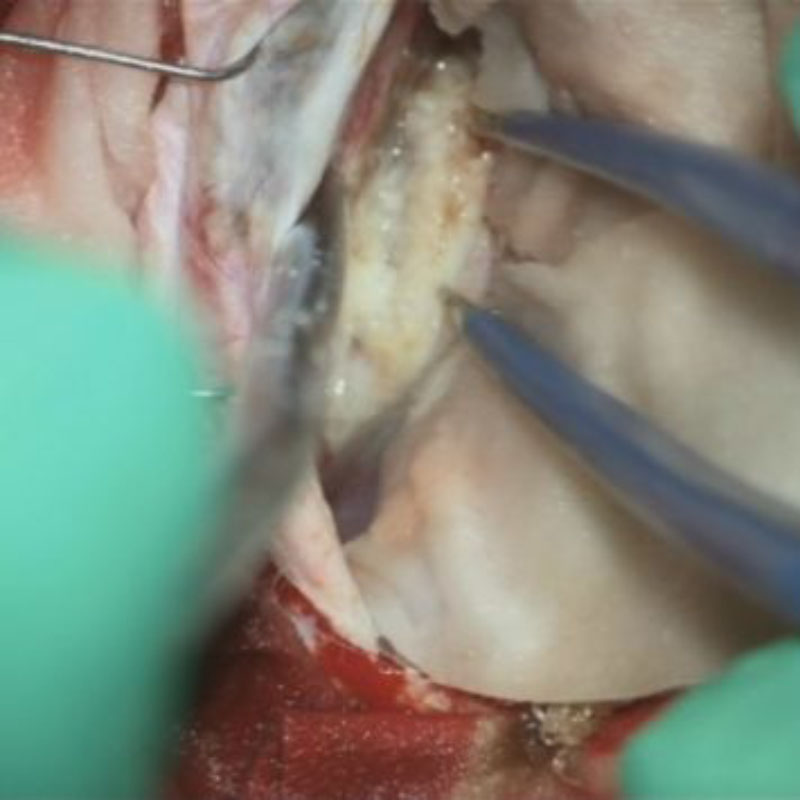

707

'25年12月

80代

髄膜腫

頭蓋内腫瘍摘出術

No.’25_109 手術前1

No.’25_109 手術前2

No.’25_109 摘出 前

No.’25_109  摘出 中

No.’25_109 摘出 後